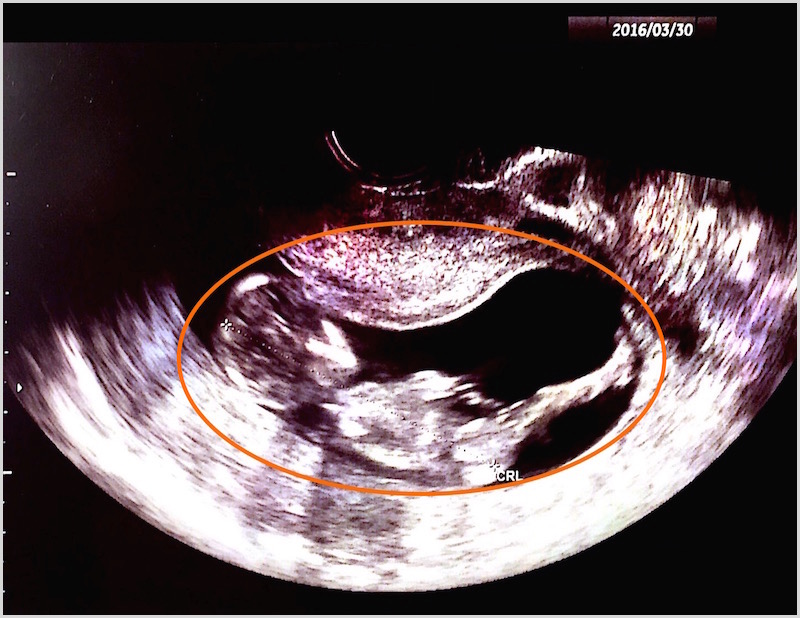

3/11(金) 30診目

10日に検診。エコー検査で問題なし。

胎児順調に大きくなっている。

3月半ば~3月末

(31診~35診・主に悪阻を診る。)

4/5(火) 36診目

12週6日目。

胎児 5.3cmになる。

頭部・手・足がしっかり確認できるように。

(↑このように寝そべった形に見えるのが胎児です。)